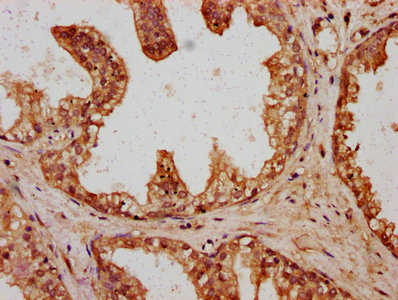

IHC (Immunohistochemistry)

(IHC image of AAA235009 diluted at 1:400 and staining in paraffin-embedded human prostate cancer performed on a Leica BondTM system. After dewaxing and hydration, antigen retrieval was mediated by high pressure in a citrate buffer (pH 6.0). Section was blocked with 10% normal goat serum 30min at RT. Then primary antibody (1% BSA) was incubated at 4 degree C overnight. The primary is detected by a biotinylated secondary antibody and visualized using an HRP conjugated SP system.)